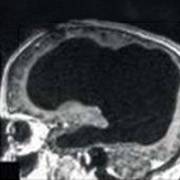

Магнитно-резонансная томография (МРТ):один из самых эффективных методов диагностики заболеваний